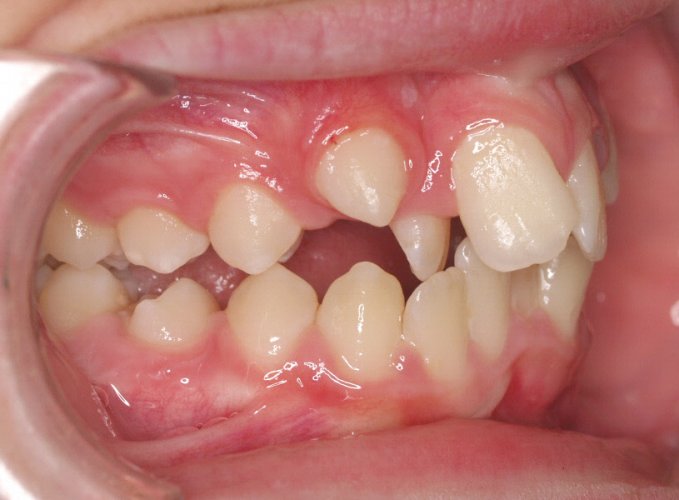

El paciente A.J. de 11 años, acude a nuestra consulta con apiñamiento maxilar importante. El canino lateral (12) está en mordida cruzada. Presenta una Clase II molar y canina, y la línea media está desviada. Se realizó un tratamiento con brackets autoligables metálicos de smartclip 022. La duración del tratamiento fue de 22 meses.

El paciente actualmente ha terminado el tratamiento con brackets y lleva una contención fija de 2-2 en maxilar y 3-3 en mandibular; para complementar también lleva una férula ESSIX durante la noche.

INICIO FINAL